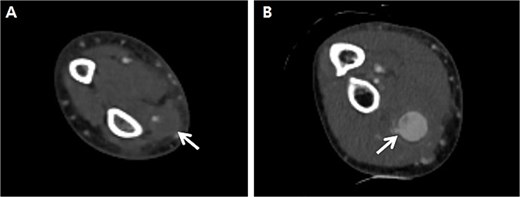

A 66-year-old male with a 1-month prior history of transradial coronary intervention visited hospital for aggravating pain and swelling on the right forearm. Upon physical exam, multiple masses were palpated at the arterial catheterization site as well as another unrelated site at the proximal forearm. An upper extremity CT scan was conducted to evaluate two different RAPs, one at the distal radial artery (arterial catheterization site) measuring 0.8 cm without a neck of pseudoaneurysm (Fig. 1A) and one at the proximal radial artery (Not related to arterial catheterization site) measuring 2.0 cm with a neck of pseudoaneurysm (Fig. 1B). Blood tests for vasculitis or autoimmune disease are not specific to confirm the possible causes of RAPs.

Preprocedural computed tomography of the right upper extremity. (A) Pseudoaneurysm at the distal radial artery which was arterial catheterization site (arrow); (B) Pseudoaneurysm at the proximal radial artery which was not related to arterial catheterization site (arrow).